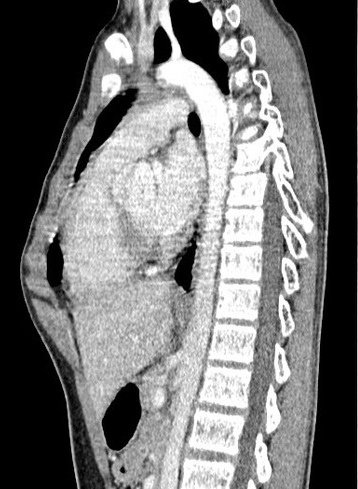

Syndrome pariétal avec lésion osseuse de hypodense

1/3 posterieure du cote droit (métastase

costale).

Image radiologique

TDM en coupe axiale |

Image radiologique TDM d'une tumeur

parietal à origine costale ( metastase costale ) |

- Lesion osseuse des metastase sur TDM souvent

hypodense

- Par la TDM on peut verifier une tumeur à

originr costale .